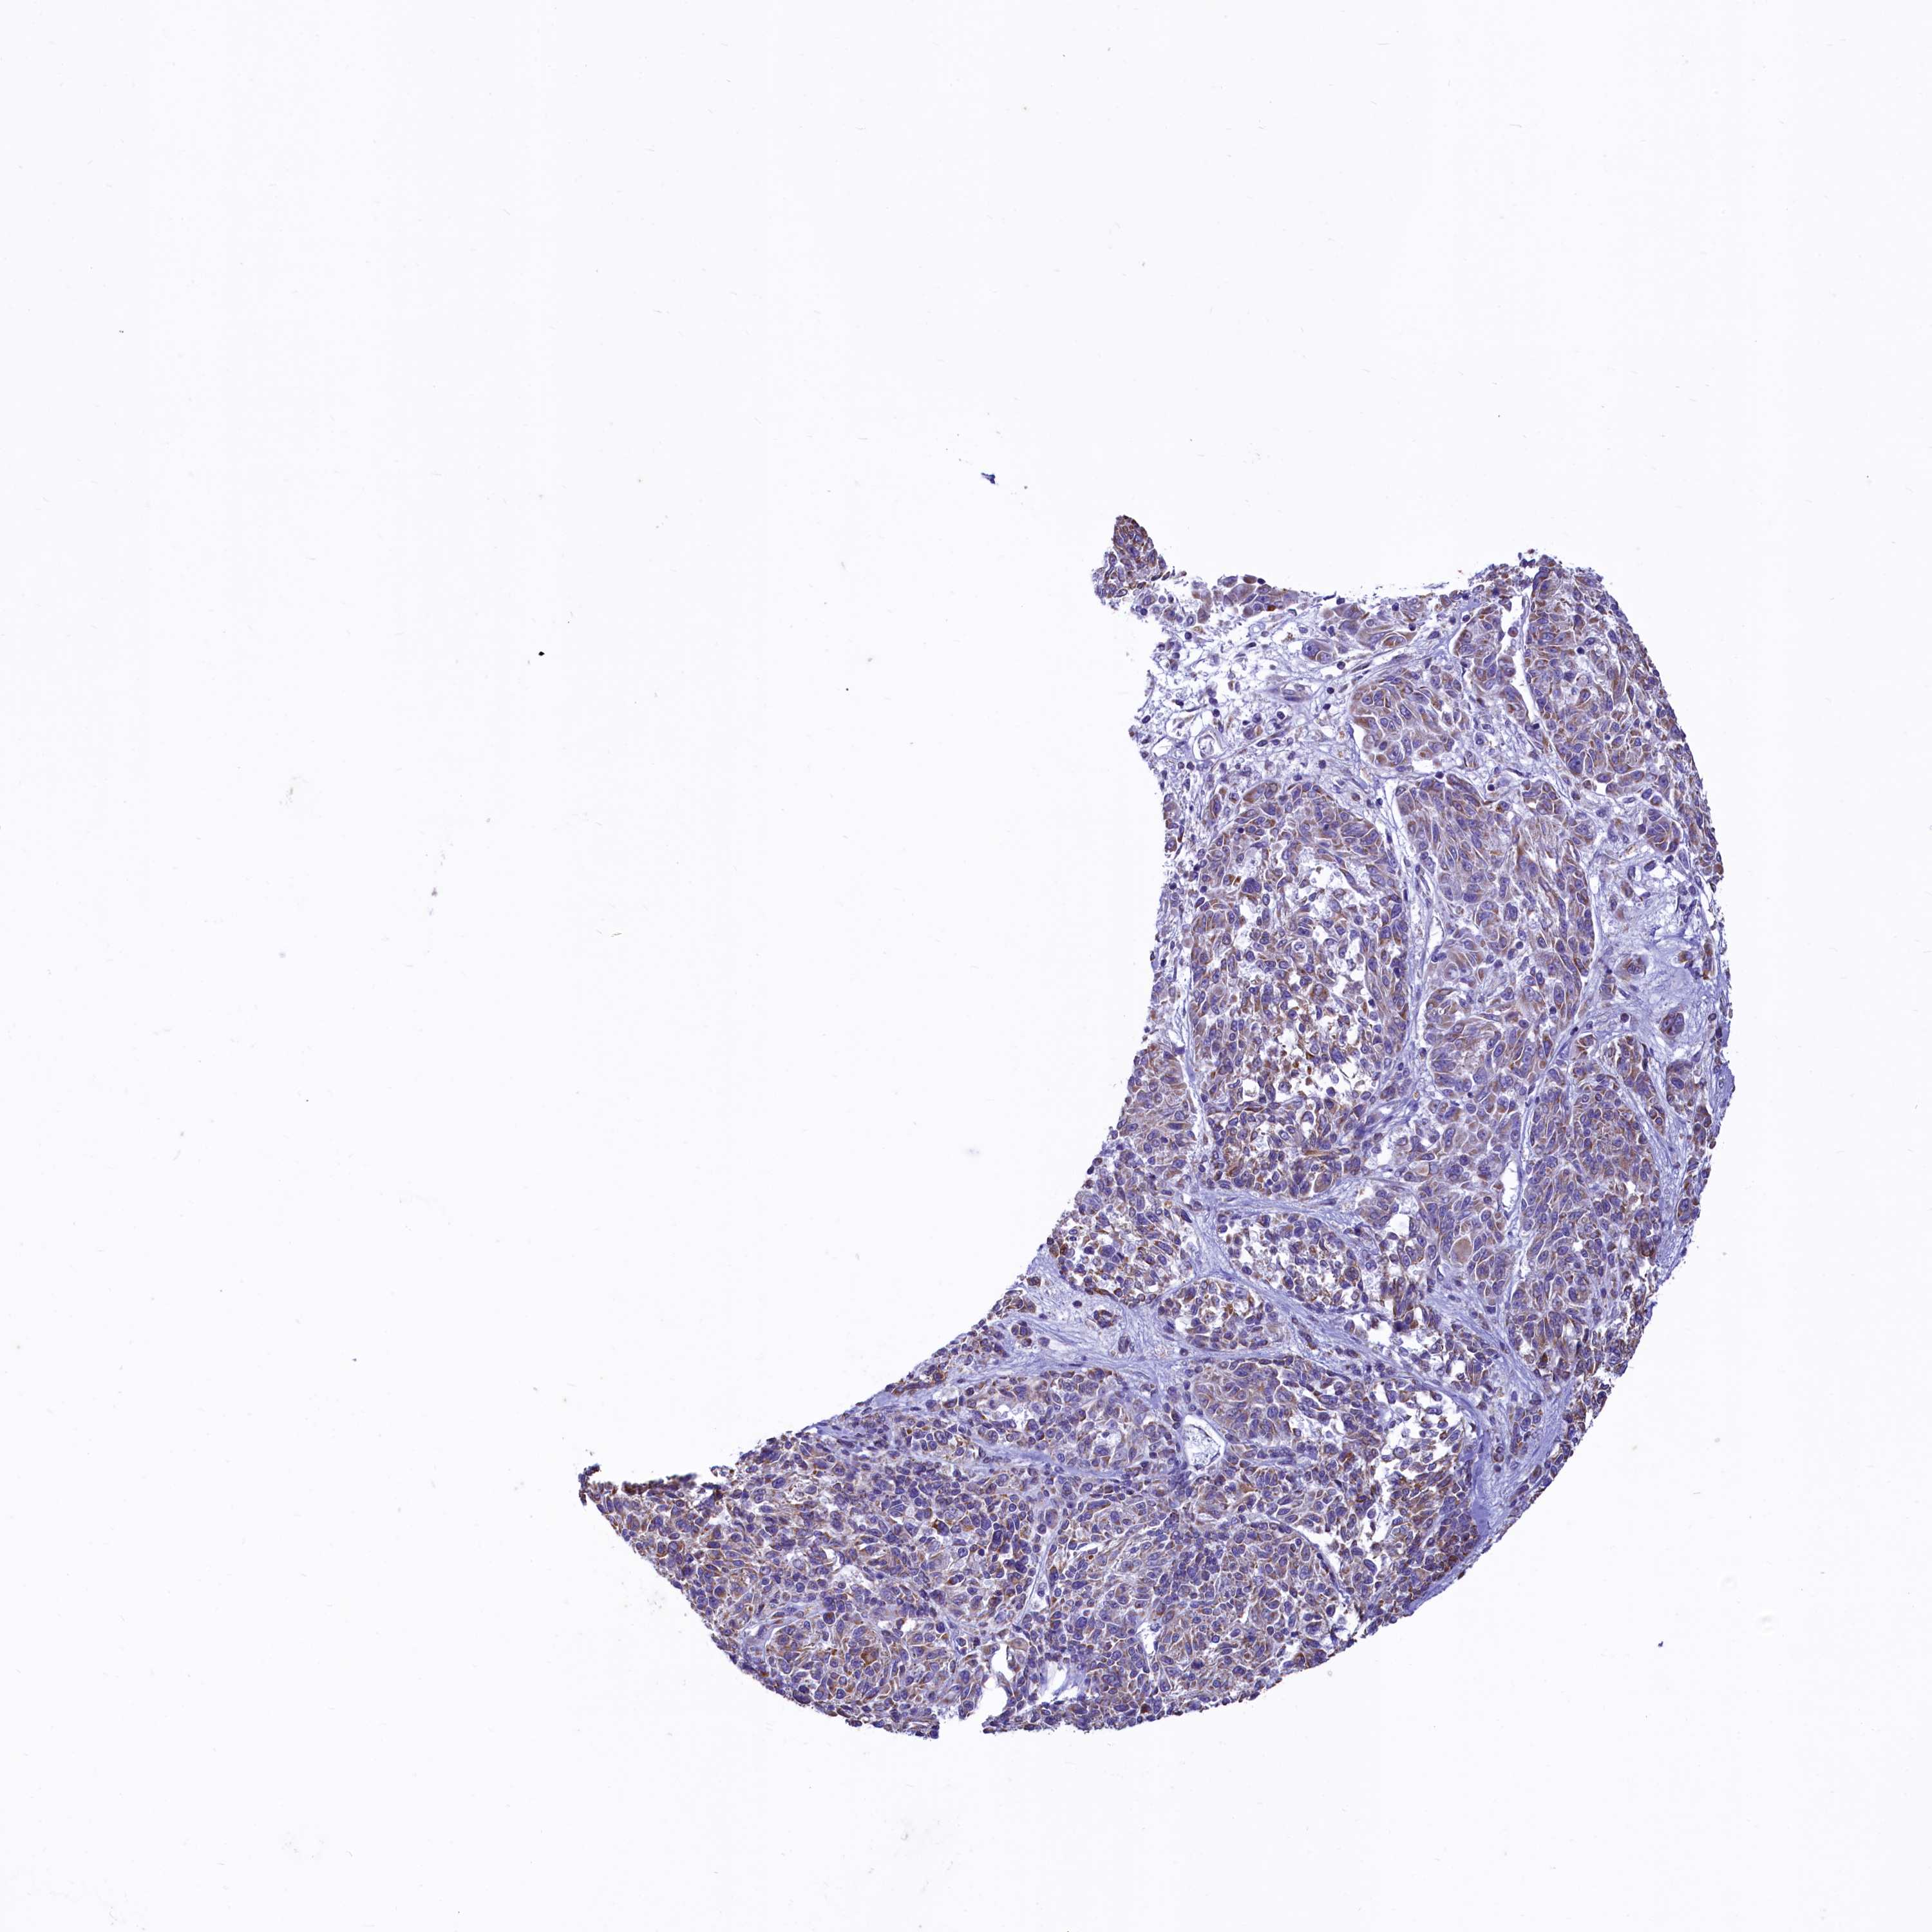

MELANOMA - Protein expressioni

A mouse-over function shows sample information and annotation data. Click on an image to view it in a full screen mode. Samples can be filtered based on level of antibody staining by selecting one or several of the following categories: high, medium, low and not detected. The assay and annotation is described here.

Note that samples used for immunohistochemistry by the Human Protein Atlas do not correspond to samples in the TCGA dataset.

Antibody stainingi

Antibody staining in the annotated cell types in the current human tissue is reported as not detected, low, medium, or high, based on conventional immunohistochemistry profiling in selected tissues. This score is based on the combination of the staining intensity and fraction of stained cells.

Each image is clickable and will lead to virtual microscopy that enables deeper exploration of all samples and also displays staining intensity scores, fraction scores and subcellular localization as well as patient and tissue information for each sample.

Antibody HPA040401

Antibody HPA043921

Staining

High

Medium

Low

Not detected

Intensity

Strong

Moderate

Weak

Negative

Quantity

>75%

75%-25%

<25%

None

Location

Nuclear

Cytoplasmic/membranous

Cytoplasmic/membranous,nuclear

Malignant melanoma, NOS

Malignant melanoma, Metastatic site